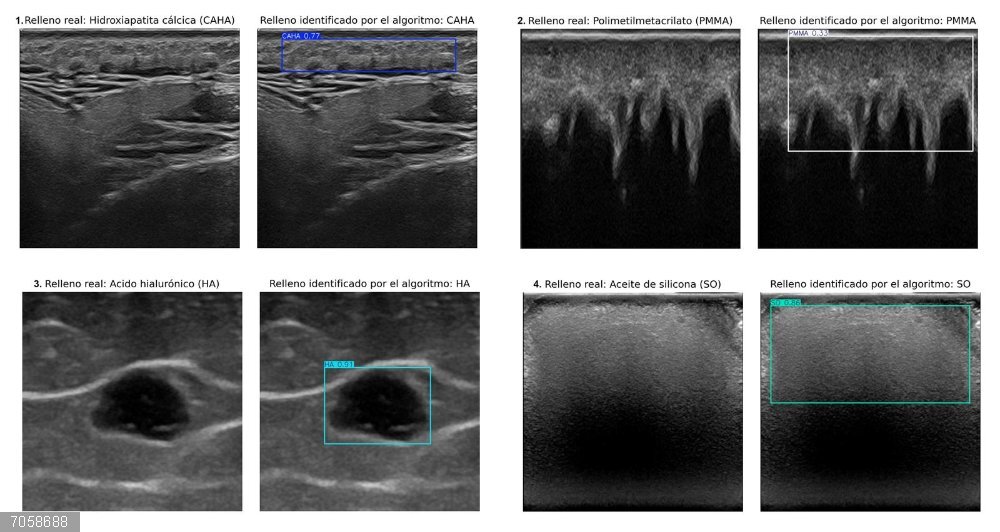

Ecografías que muestran rellenos estéticos identificados por un especialista (izquierda) y las regiones detectadas por el algoritmo (derecha). En los cuatro casos, el algoritmo acertó en clasificar y delimitar el área de cada relleno.